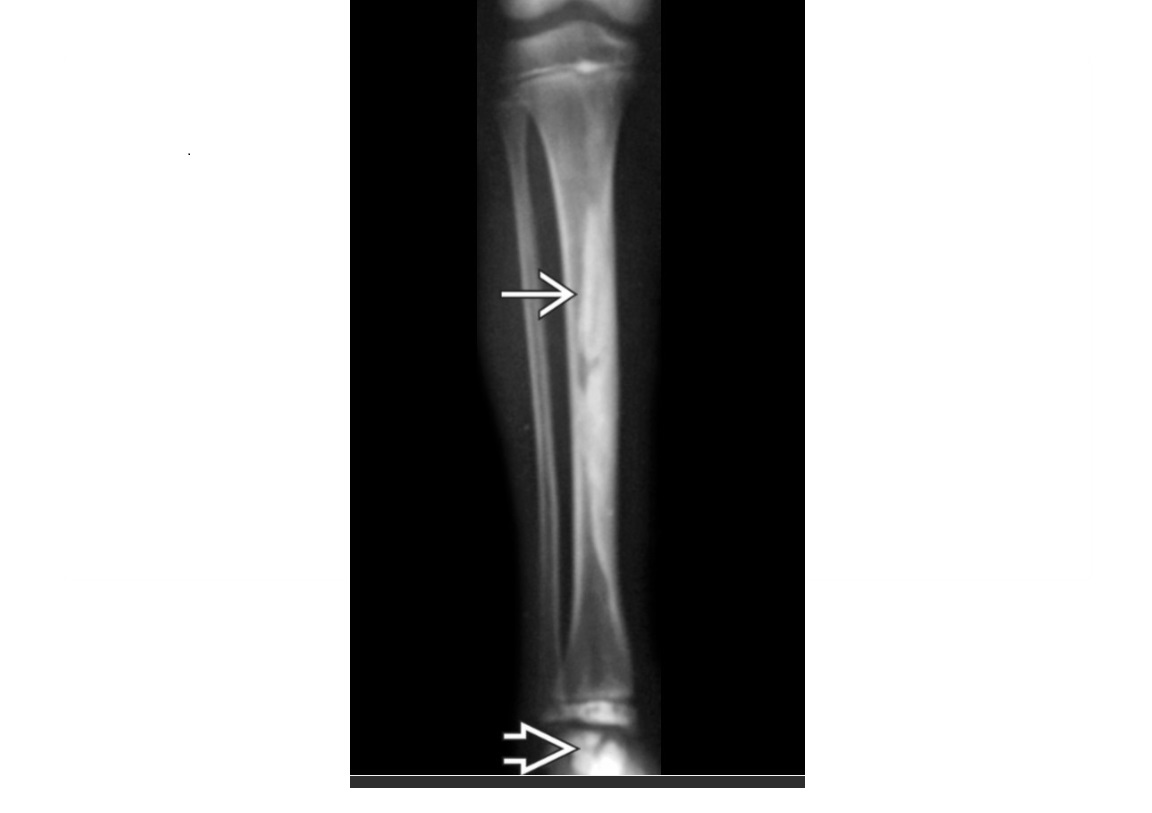

Adamantinoma

Low-grade, malignant lesion most frequently arising in tibial** cortex**

Mutlifocal

slcerotic and lytic compoents

*Cortically based lesion in anterior tibia